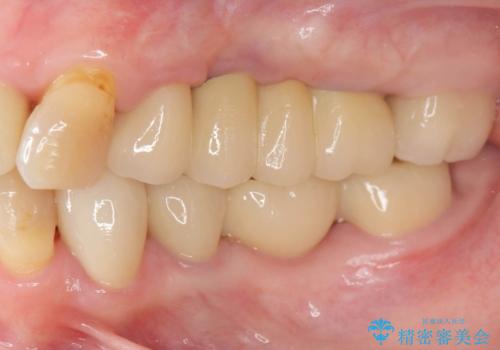

期間は約2年ほどかかりましたが、審美的な仕上がりとともに清掃のしやすさも非常に満足いただくことができました。